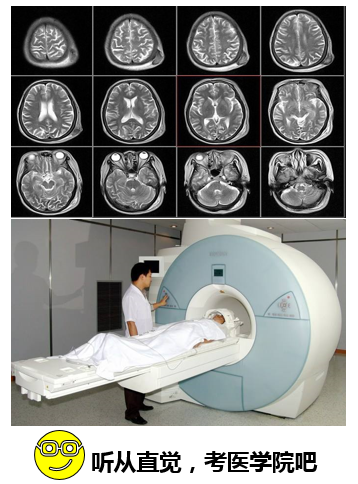

如果你想到的是像核磁共振、核医学检测、放射性医学检测,那么你可以听从你的直觉,未来去从事医学,去报考医学院。

第二块的应用是核技术在医学诊断中的应用。我们知道像医学影像包括像CT的、核磁的、超声的等等这些成像方式。也有另外一块叫做核医学成像,它主要是利用放射性的药物注射到人体内进行代谢,我们通过对放射性的药物进行影像显像,来体现出人体病灶、代谢的位置等等。那么像我们熟悉的SPECT/CT、PET/CT等等,这些影像的设备就是属于此类的核技术的应用。